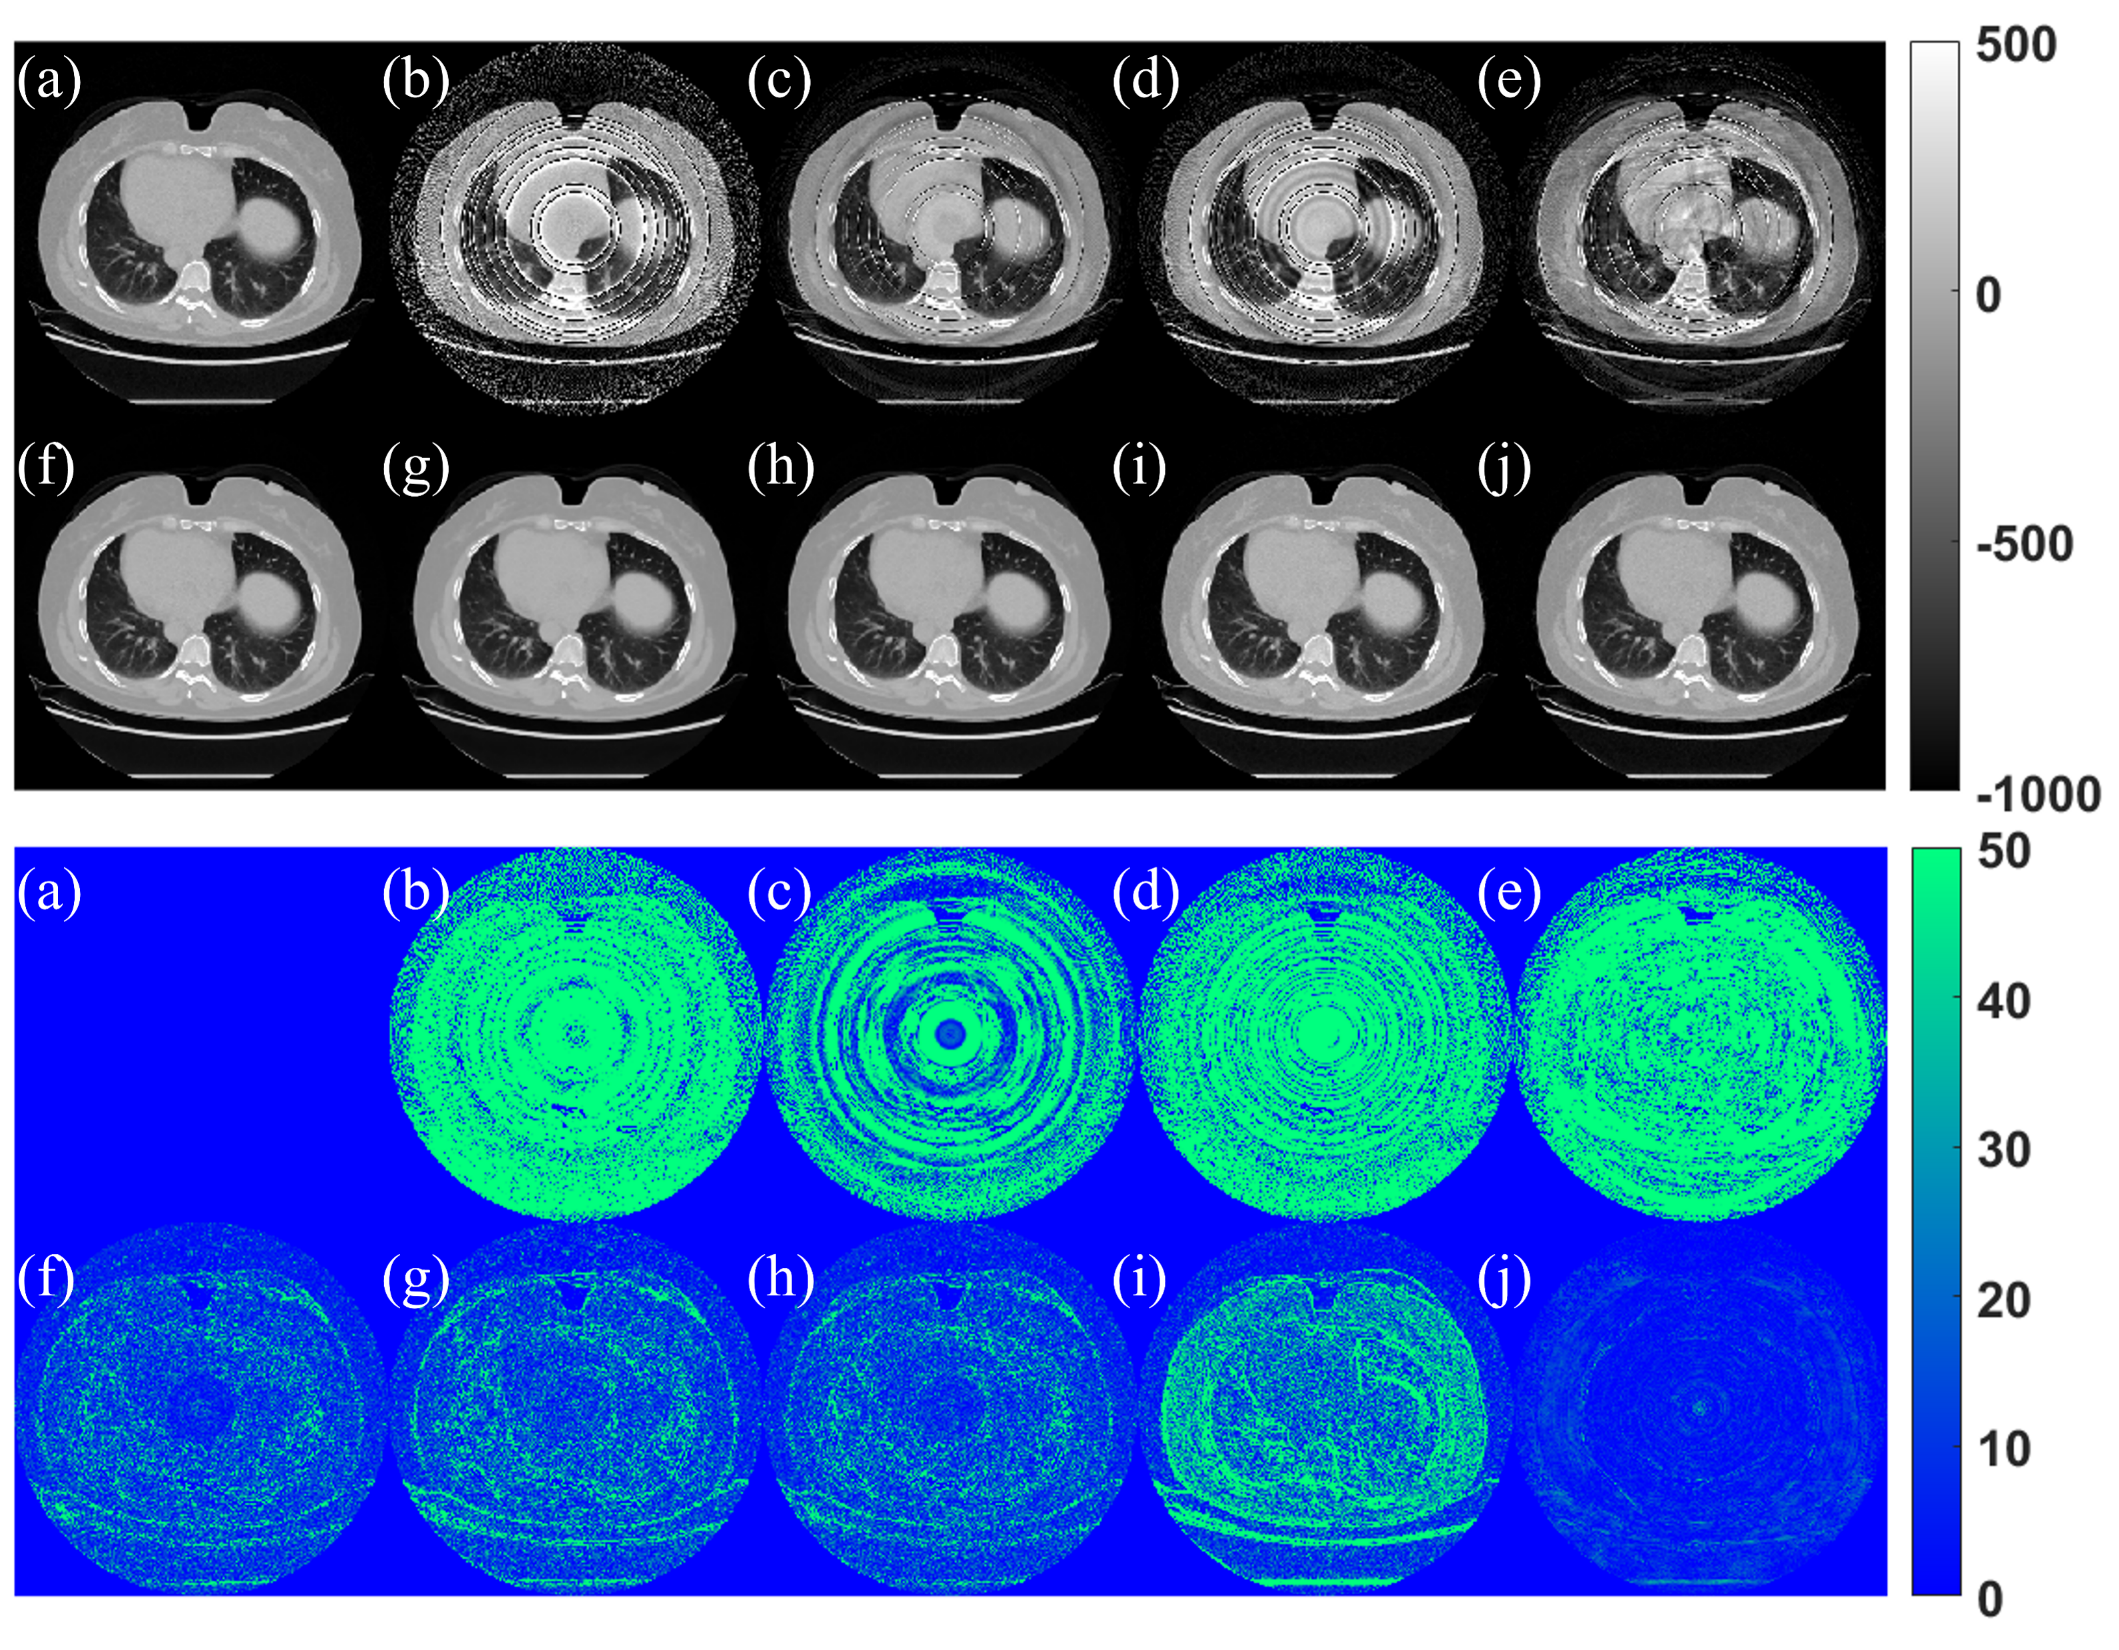

Refer to caption

Figure 6: Qualitative comparison for RAR methods: (a) Ground truth, (b) FBP, (c) Norm, (d) WaveFFT, (e) Super, (f) AST, (g) DeepRAR (h) NAFNet, (i) Riner, and (j) SynthRAR. Top: images in HU value. Bottom: absolute HU value differences to ground truth.

Figure 7: Profile analysis in image domain (row 128), corresponding to images from Fig. 6. The enlarged region spans pixel indices between 200 and 300.